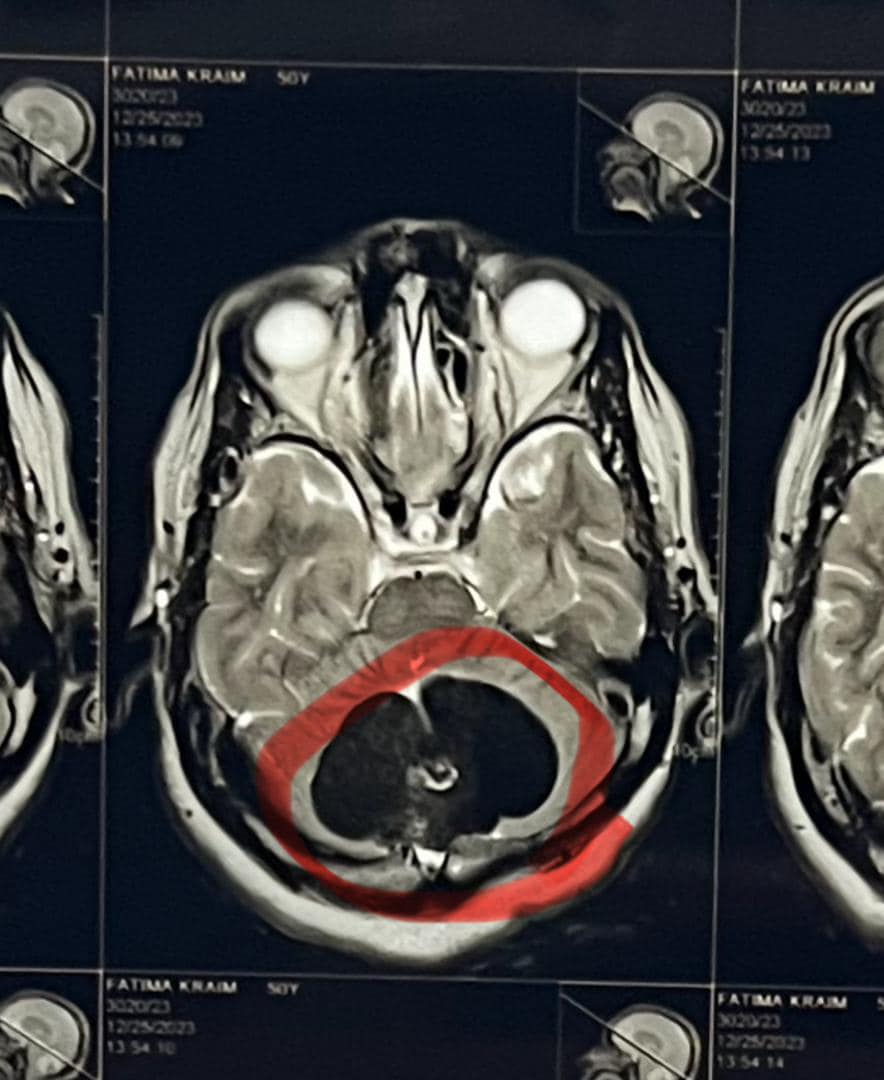

سرت 22 يناير 2024 م (الأنباء الليبية) – أجرى فريق طبي من جراحي المخ والأعصاب بمستشفى بن سينا التعليمي بمدينة سرت عملية جراحية ناجحة لإنقاذ حياة مريضة من مدينة زليتن تبلغ من العمر 60 سنه كانت تعاني من ورم دماغي كبير منذ فترة ستة أشهر نتج عنه صداع شديد ومزمن في الرأس وأفقدها القدرة على المشي بشكل متوازن.

وأوضح رئيس الفريق الطبي الدكتور الإخصائي عبد الفتاح الغويل، أن العملية استغرقت أكثر من 3 ساعات وتم خلالها استئصال الورم الدماغي بالكامل بنجاح وأكد أن السيدة تتمتع حاليًا بصحة جيدة ويتوقع أن تتعافى تمامًا من العملية خلال فترة لا تتجاوز يومين.